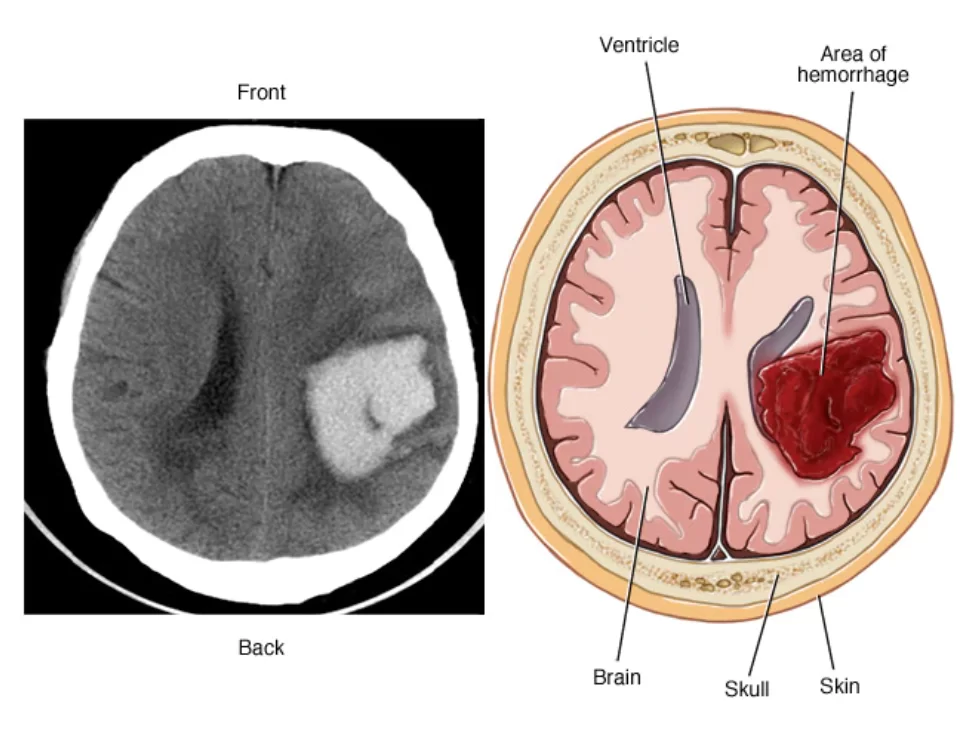

Όταν αναφερόμαστε στην εγκεφαλική αιμορραγία (αιμάτωμα στο κεφάλι), μιλάμε για τη συλλογή αίματος εντός του εγκεφαλικού παρεγχύματος, δηλαδή εντός του εγκεφάλου. (Σε αντίθεση με άλλες αιμορραγίες οι οποίες στην πραγματικότητα είναι μεν εντός του κρανίου αλλά εκτός του εγκεφάλου όπως πχ. το επισκληρίδιο ή υποσκληρίδιο αιμάτωμα). (Εικόνα 1)

Η εγκεφαλική αιμορραγία είναι μια επείγουσα κατάσταση και απαιτεί άμεση διάγνωση. Η αξονική τομογραφία είναι η πιο σημαντική εξέταση γιατί μπορεί με βεβαιότητα να βάλει ή να αποκλείσει τη διάγνωση της εγκεφαλικής αιμορραγίας. Δίνει επίσης πληροφορίες για το μέγεθος και τη θέση της αιμορραγίας, για την παρουσία ενδοκοιλιακής αιμορραγία (δηλαδή αίματος εντός των κοιλιών του εγκεφάλου), την παρουσία οιδήματος, αν υπάρχει παρεκτόπιση των δομών της μέσης γραμμής κ.ο.κ.